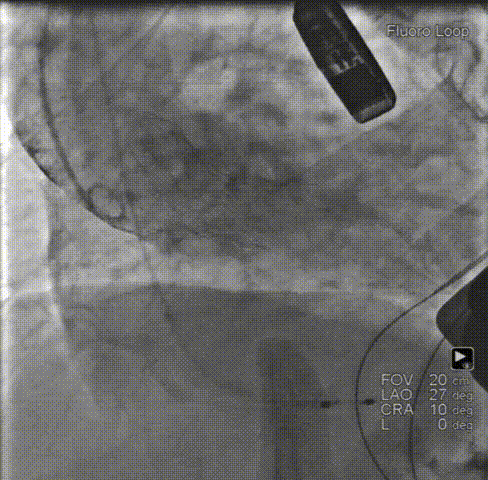

瓣膜释放前根部造影瓣膜打开到80%,再次行主动脉根部造影,支架高度和植入深度满意,不需要回收,直接释放瓣膜。

释放瓣膜:0位匀速释放Xcor-26瓣膜流入端。

后扩张:22mm球囊后扩张,支架膨胀形态良好,未见支架回弹,未见移位。

术后造影:最终主动脉根部造影示支架瓣膜释放位置佳,瓣叶运动良好,支架内未见明显反流,轻度瓣周漏。